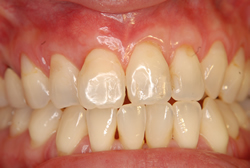

症例1【50代女性】主訴・前歯4本の根が見えるのが気になる。根面被覆(Root coverage)口蓋(上顎)から歯肉を採取し、露出している根面に歯肉を移植し被覆。

治療後

根面被覆(Root coverage)口蓋(上顎)から歯肉を採取し、露出している根面に歯肉を移植し被覆。

露出が目立たなくなり、歯肉のラインもきれいに改善された。

費用 10万(歯肉移植術)